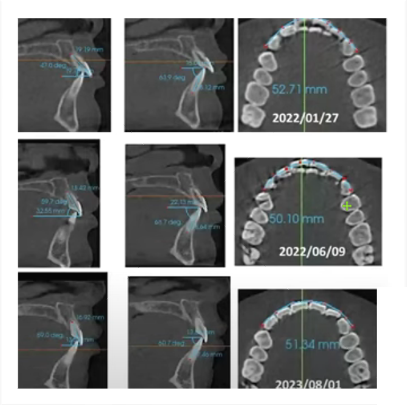

Occlusal line angle and maximum cusp position of upper and lower teeth

- Patent notice for tooth arrangement and production method of Maximal Intercuspation Position (MIP) occlusal line angle and maximum cusp position of upper and lower teeth

- The concept of Maximal Intercuspation Position (MIP) is the basis of the field of dentistry and orthodontics. However, it is challenging to pinpoint exactly when these ideas were first proposed because they have been developed and refined over a long period of time.

- occlusal line angle

- The occlusal angle line refers to the angle formed by the occlusal plane, which is essentially the imaginary surface where the upper and lower teeth come into contact during biting and chewing. This concept has been around for a long time and is critical to understanding bite mechanics, jaw alignment, and orthodontic treatment planning.

- Maximal Intercuspation Position (MIP) of the upper and lower teeth

MIP, also commonly referred to as "center bite," is the position where the upper and lower teeth come together in an optimal or "maximum" bite. This is an important concept in diagnosing and treating malocclusion as well as restorative dentistry.

- According to the development of this concept, the use of digitally built occlusal retainers (positioners) on the articulator to control the growth and occlusal alignment of teeth can be accomplished based on the occlusal angle line.

- line angle與建立上下牙齒的最大尖窩位置 Maximal Intercuspation Position(MIP) ,根據這個方法申請專利,成為首個製造出咬合與排牙兼具的COMiP牙套。

- 正式收專利公告通知,以咬合線為基準的排牙法,是一種齒列橋正牙套及其製造方法,該齒列橋正牙套可用於進行牙科矯正。該製造方法需取得上 顎下顎的齒位構造圖,並透過牙科軟體讀取 、顯示該齒位構造圖,將上顎牙齒的多個窩凹連成 一上咬合線的弧線,將下顎牙齒的多 個齒尖連成一下咬合線的弧線, 再透過該上下咬合線而生成一矯正弧線,進而生成尖窩對應的上顎矯正槽位及下顎矯正槽位,再以之生成該齒列橋正牙套的上下顎對應件,再用以矯正牙科病患齒列不正的問題 。

- We have officially received a patent notice. The tooth arrangement method based on the bite line is a dental bridge brace and its manufacturing method. The dental bridge brace can be used for dental correction. This manufacturing method requires obtaining the tooth structure diagram of the upper and lower jaws, reading and displaying the tooth structure diagram through dental software, connecting the multiple fossa of the upper jaw teeth into an arc of the upper occlusal line, and connecting the multiple cusps of the lower jaw teeth. The cusp tips are connected to form an arc of the bite line, and then a correction arc is generated through the upper and lower bite lines, and then the upper jaw correction slot and the mandibular correction slot corresponding to the cusp fossa are generated, and then the dentition bridge is generated. Orthodontic braces are matching parts for the upper and lower jaws, and are used to correct the problem of dental misalignment in dental patients.